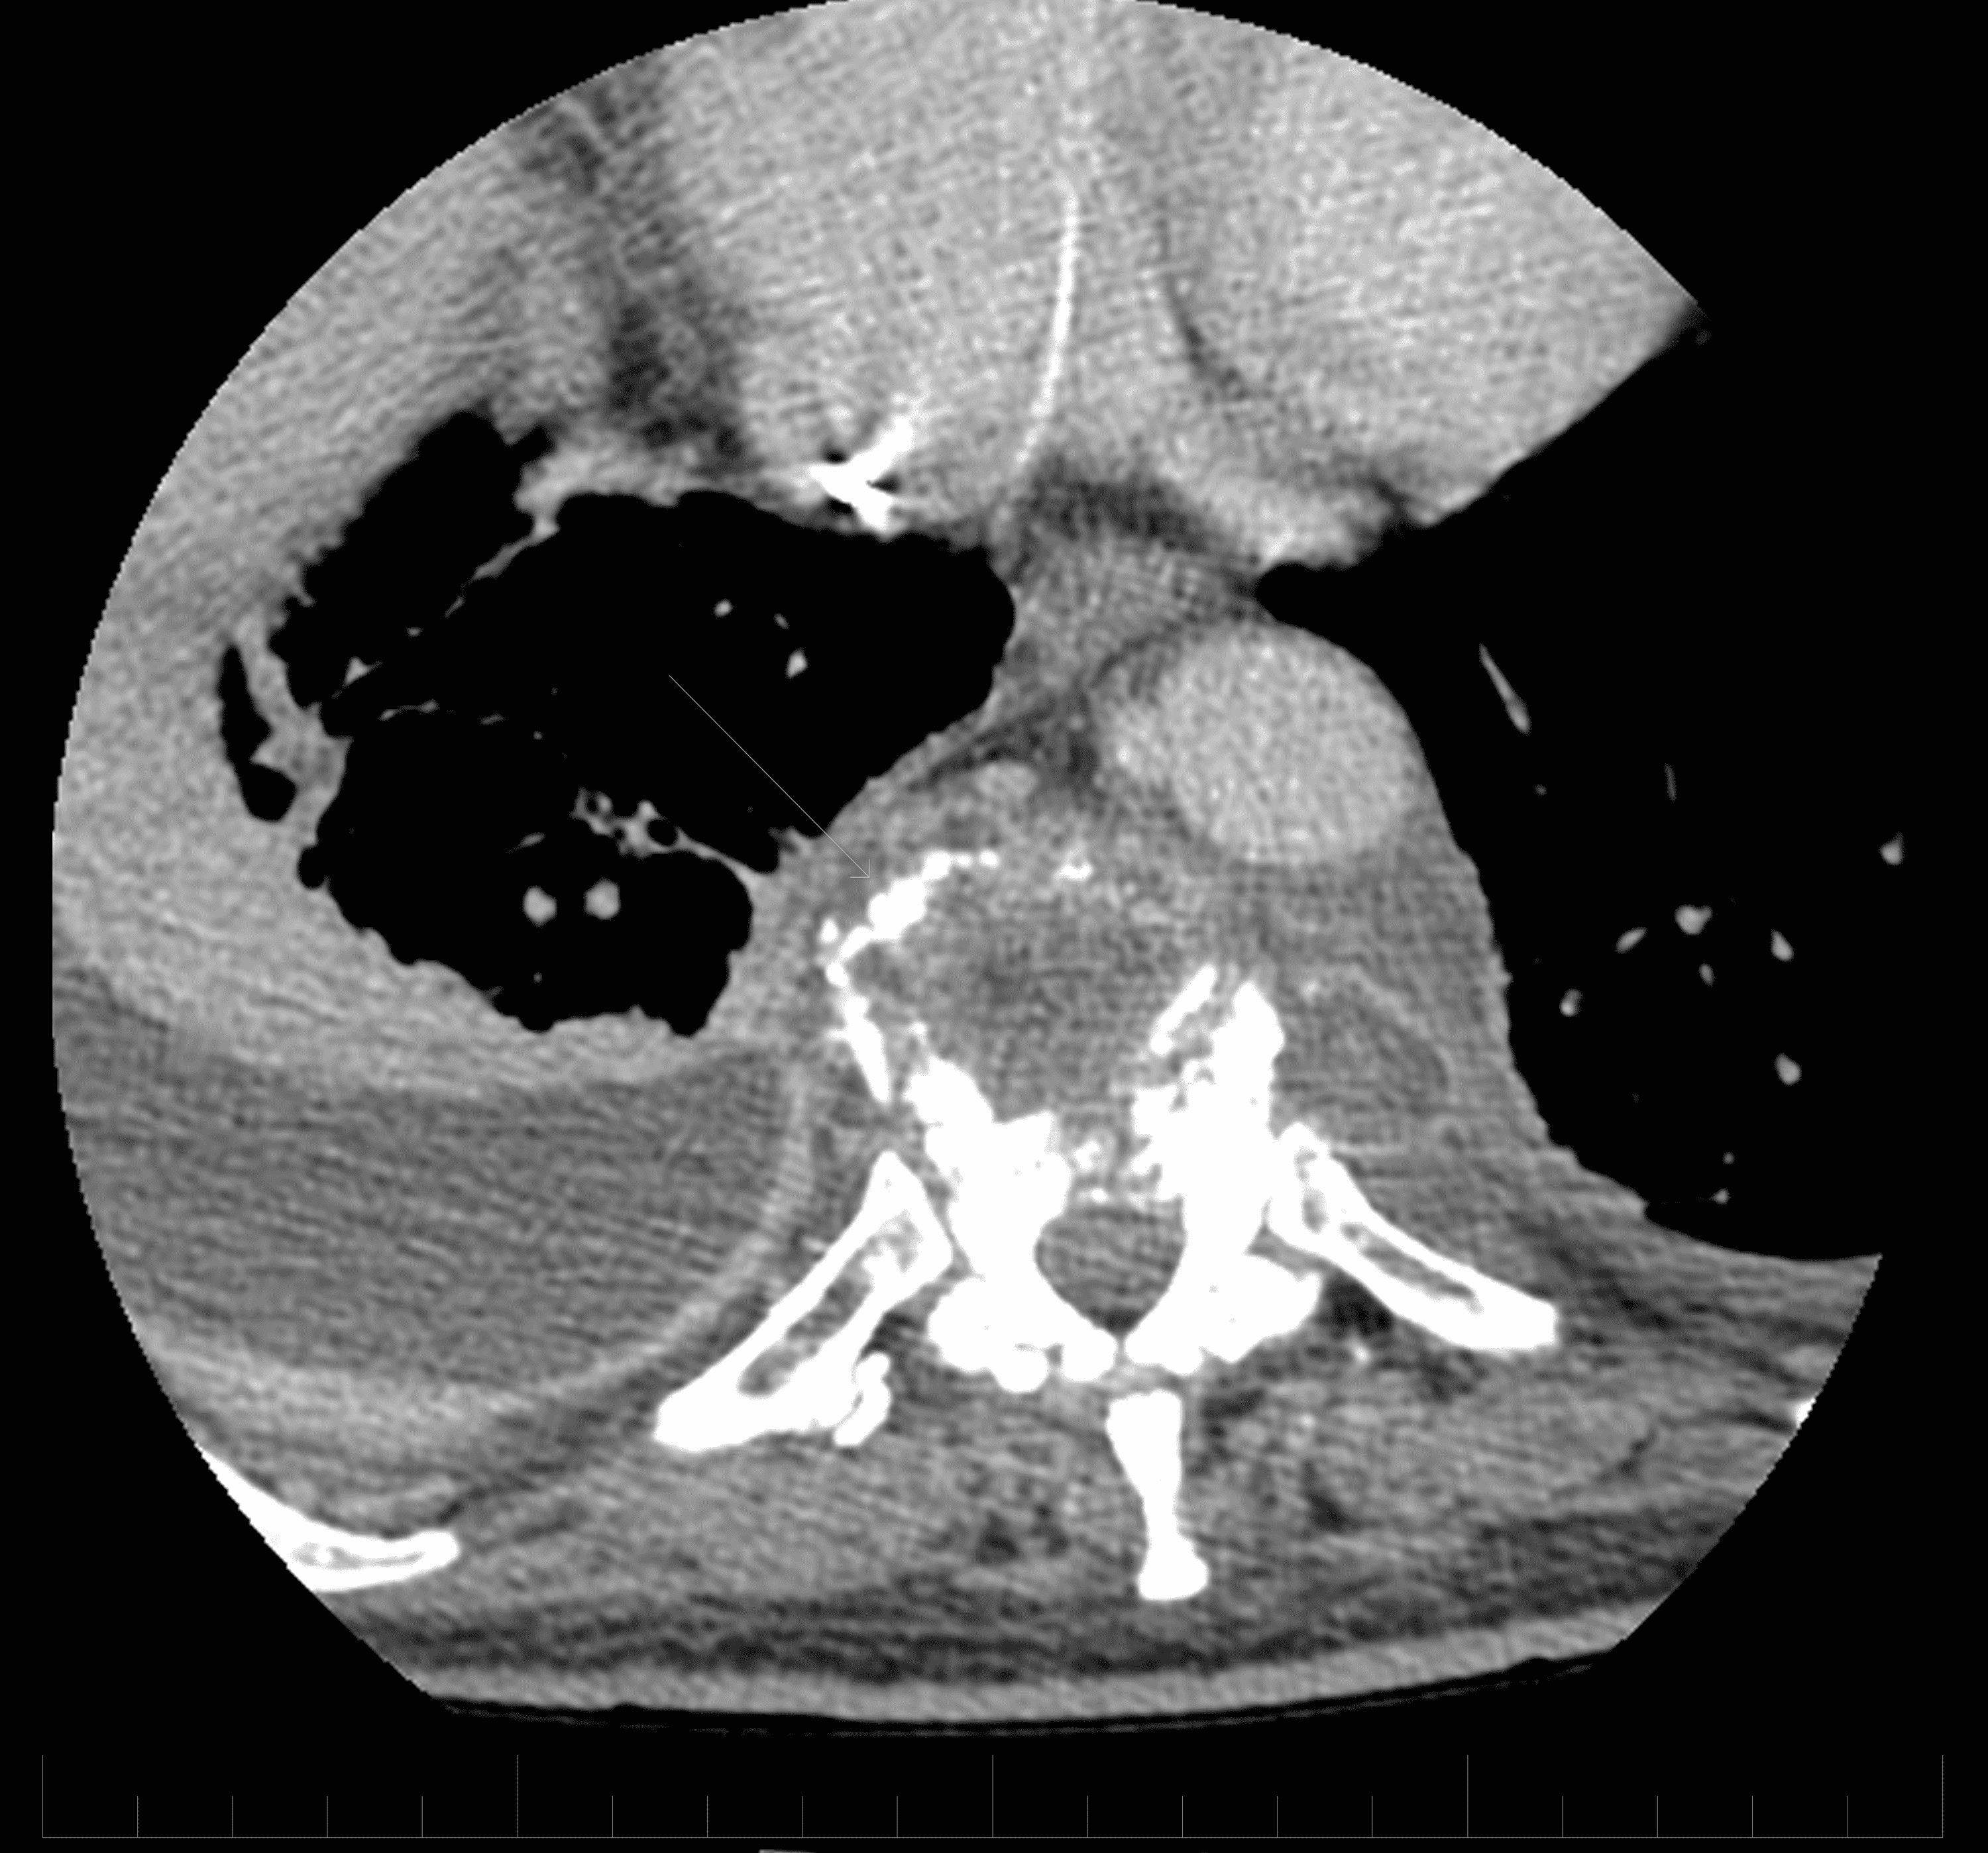

From www.wikidoc.org

Pott's disease CT wikidoc Is Pott's Disease Deadly Tuberculous spondylitis occurs due to an infection with the mycobacterium. causes and risk factors. a common form of spinal bone tb is known as pott’s disease. Early detection is key for improved prognosis. tuberculosis can be deadly. Bone tb occurs when you contract. while the current literature shows that timely diagnosis is crucial to reduce the. Is Pott's Disease Deadly.